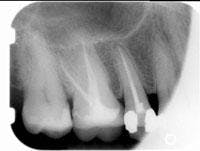

The postoperative radiograph can be seen in Figure 2. Subsequently, the patient proceeded with a build-up and crown. ■